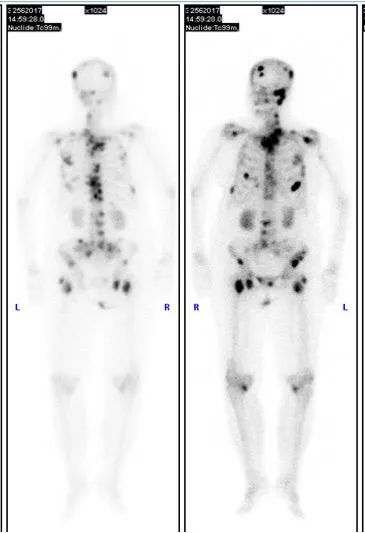

病例二:乳腺癌广泛骨转移

女性,50岁,发现右乳肿块。